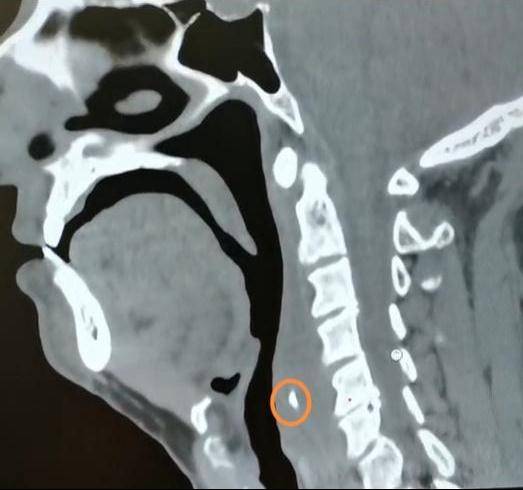

近日 , 家住饶河的王先生在家吃“嘎牙子”鱼时 , 不小心被鱼刺卡住了喉咙 , 但王先生并没有当回事 , 喝了几口醋 , 吞了馒头想把刺“推”下去 , 结果却不如人意 , 喉咙越来越疼了 。 王先生又用了几天消炎药后仍是疼痛难忍 , 于是去了当地医院 , 做颈部CT检查 , 结果显示鱼刺完全没入软组织内 。 经多方打听 , 王先生来到哈医大四院就诊 。

经过详细检查 , 哈医大四院耳鼻咽喉头颈外科主任周彬为王先生进行急诊全麻下支撑喉镜下下咽后壁切开异物取出术 。 术中可见咽后壁粘膜光滑 , 会厌高度偏左侧的咽后壁略隆起 。 在隆起处以激光纵行切开粘膜及粘膜下组织 , 脓性液体流出 , 其内可见一白色鱼刺 。 完整取出鱼刺 , 可见其上端呈针尖状 , 整体呈弧形 , 边缘锐利光滑 , 无破损 。 术后 , 王先生恢复良好 。